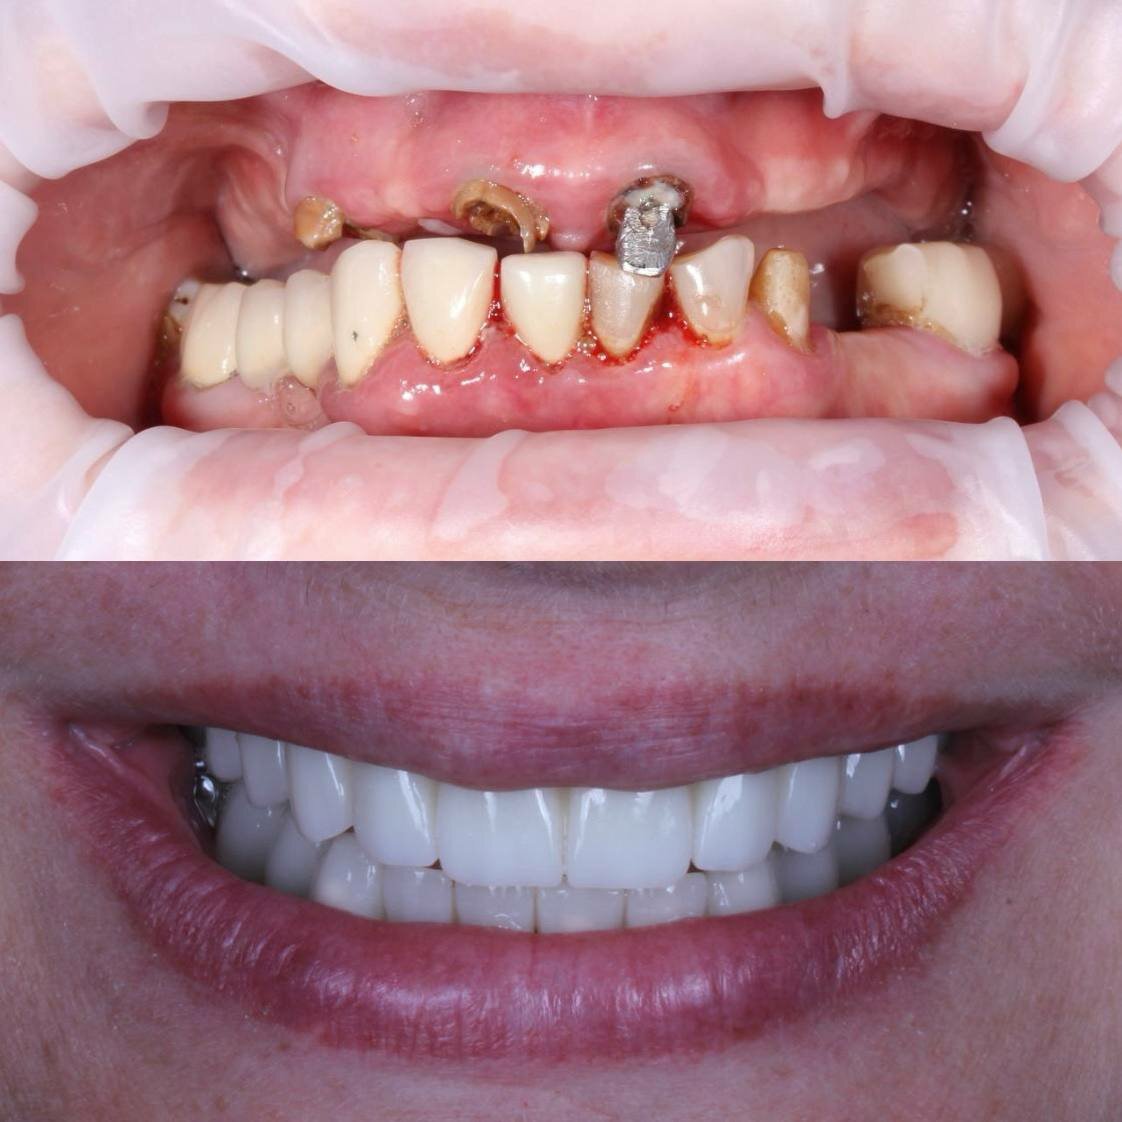

- Долговечные и эстетичные результаты (импланты, протезы).

Приходила на очередной осмотр, прошло уже больше 5 лет как Гилязов Булат Ильгизович установил мне мои зубы. К зубам быстро привыкла, своих зубов оставалось очень мало, наверное, 5 зубов всего, думала, что и их придется удалить, были некрасивые, разрушенные. Булат Ильгизович сказал, что в моем случае надо сохранить все зубы, которые хотябы еще могут прослужить больше 5 лет, так как у меня очень маленькие кости и возможности установить импланты нет. Наращивать кость в моем случае тоже было нежелательно. Несмотря на такую ситуацию зубы получились очень даже хорошими, по цвету натурально белоснежные, ровненькие, постоянно спрашивают кто мне сделал такие красивые зубы. Я очень благодарна за такую безупречную работу, потому что много у кого вставные зубы выглядят как не живые, большие. Желаю процветания клиники, врачам, каждый год прихожу на осмотр, делаем чистки, бережем, что осталось.